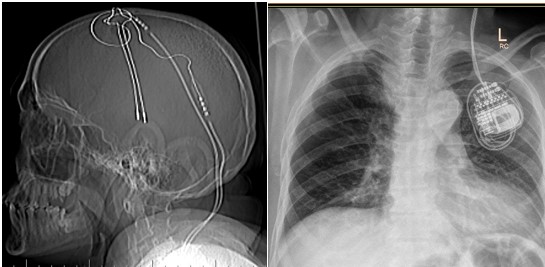

2. Xray of Head (AP and lateral) and contiguous Chest x ray was done which showed continuity of the lead wires into the battery.(FIGURE 1)

FIGURE 1